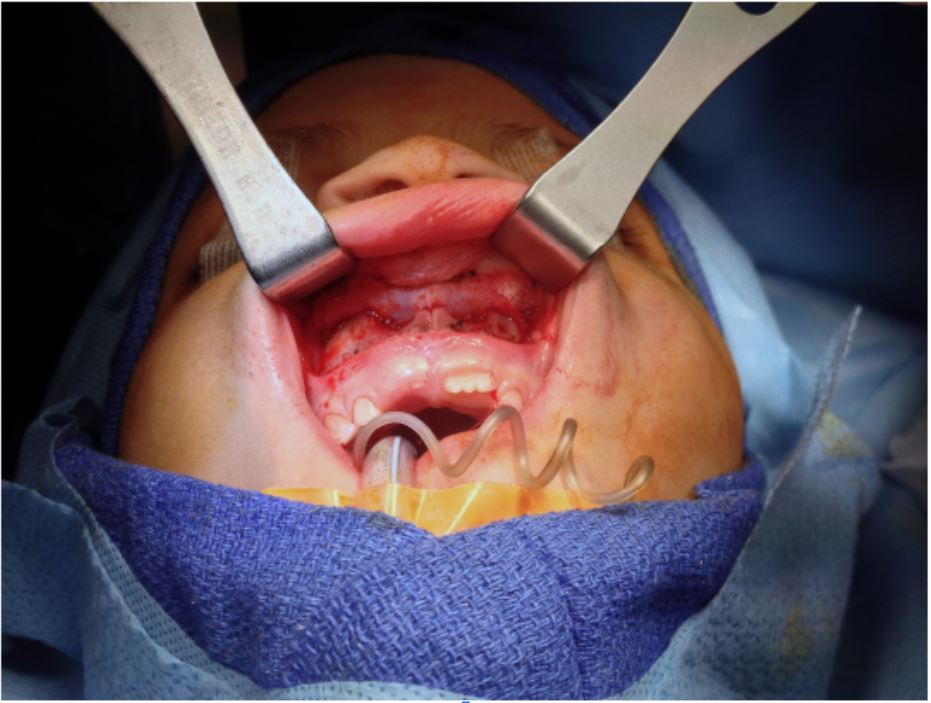

Following endotracheal intubation and appropriate sterile preparation of the nose and face, an upper gingivobuccal sulcus incision was carried down to the maxillary periosteum (Figure 2). A subperiosteal dissection was then performed to the level of the piriform rim and anterior nasal spine, elevating the lateral vestibular mucosa and nasal floor in continuity as a wide-based mucoperiosteal flap. Dissection was carried out at this depth, medially raising the mucoperichondrium off the caudal septum and the mucoperiosteum off the vomer up to level of the septal perforation. An incision was then made around the circumference of the perforation, followed by separation of the mucoperichondrium bilaterally covering the cartilaginous septum (Figure 3). By en bloc elevation, the mucoperichondrium from the lateral vestibule/piriform and nasal floor were advanced medially, effectively closing the perforation in a straight, tension-free bilateral closure from posterior to anterior (Figure 4). An interposition graft of human acellular dermal matrix (AlloDerm, LifeCell Corp) was then inset, and the caudal septum was affixed to the maxillary spine to prevent displacement. Lastly, the gingivobuccal sulcus incision was closed, and silicone nasal splints were placed using transeptal suture fixation.

Figure 2. Upper buccal sulcus incision allows exposure to the anterior nasal septal perforation and local tissue advancement and closure.